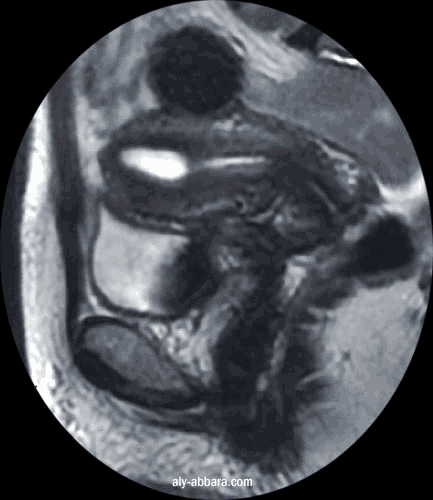

Fibrome utérin (myome) sous séreux pédiculé asymptomatique

(pédicule court et large)